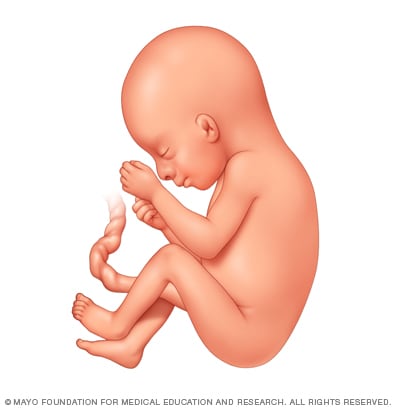

Иконки и символы, связанные с эмбрионом

Раздел: Образы вокруг